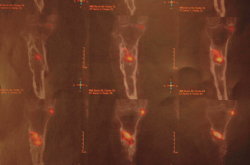

Tras estudio de tomografía computarizada de emisión monofotónica (SPECT-TAC) y gammagrafía con leucocitos marcados, se objetiva foco séptico al nivel del extremo proximal de la tibia (Figura 3).

Figura 3. Estudio de SPECT-TAC-gammagrafía con leucocitos marcados. Se objetiva captación compatible con proceso séptico en el extremo proximal de la tibia.